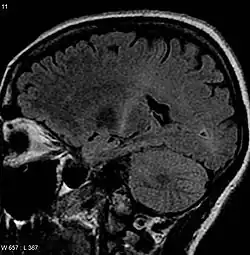

W mózgu chorych w barwieniach na obecność mieliny można uwidocznić demielinizację w drogach korowo-rdzeniowych, a także uszkodzenie neuronów. Zmiany są dobrze odgraniczone i zajmują pęczki boczne rdzenia. Uszkodzenie dotyczy też jąder ruchowych nerwów czaszkowych, zwłaszcza jądra nerwu podjęzykowego. Zmiany w korze mózgowej dotyczą komórek piramidowych zakrętu przyśrodkowego, w rdzeniu kręgowym (przede wszystkim jego odcinku szyjnym i lędźwiowym) stwierdza się ubytki ilościowe neuronów dużych i średnich rogów bocznych, a także cechy morfologiczne uszkodzenia neuronów: tigrolizę, obkurczenie komórek, jądra piknotyczne, odkładanie się złogów wewnątrzcytoplazmatycznych. Wtręty cytoplazmatyczne są objawem patognomonicznym dla ALS. Wyróżnia się kilka ich rodzajów: